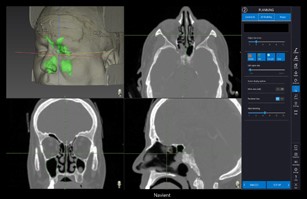

Planning

Build 3D model of sinus (Optional)

• 3D sinus modeling and navigation

• Smart 3D automatic front clip